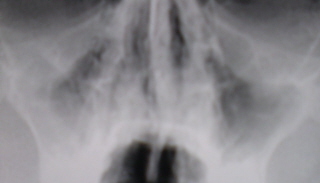

На иллюстрации 11 определяется выраженное объёмное уменьшение правой гайморовой полости за счет концентрической облитерации её. Структура пристеночного затемнения в виде довольно широкой полосы, неоднородной структуры, что свидетельствует не о «банальном» отёке слизистой, а о разрастании фиброзной ткани. Слева в гайморовой полости аналогичный процесс – неоднородное снижение прозрачности гайморовой пазухи, с преимущественным разрастанием фиброзной ткани медиально, базально и латерально.